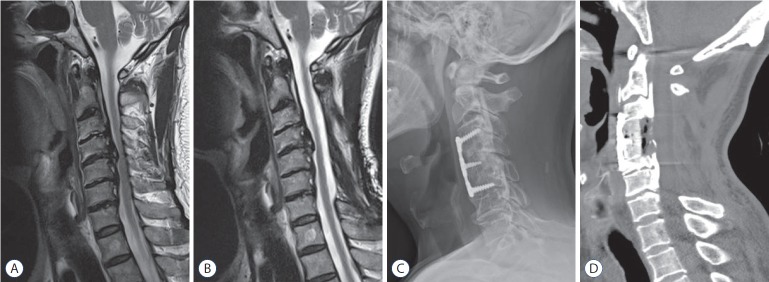

The occurrence of neurological symptoms in group PA was mainly caused by a progression of kyphosis in cervical curvature, even though there was the progression of OPLL. This mechanism differs from that of group AP, in which the majority of main OPLL lesions were removed during initial anterior surgery; progression of OPLL at a different segment led to neurological symptoms (Fig. 2). In group PA, neurological decompression had already been achieved in multiple segments during the initial posterior surgery, and progression of remnant OPLL at a different segment does not play as significant a role in development of neurological symptoms as in group AP (Fig. 3).

Fig. 3.

Case 2 (group PA). A male patient, 59 years of age, underwent laminectomy alone on C3–6 for OPLL of C3–6 causing myelopathy including gait disturbance and numbness of both arms (A). The symptoms was relieved and maintained for 30 months. However, he presented of gait disturbance and weakness of upper limbs again. The OPLL lesion of C4–5 continued as the main pathology causing initial myelopathy and newly developed symptoms with a progression of cervical kyphosis (the entire cervical Cobb’s angle from 1.9 to -9.0) (B). Anterior cervical corpectomy and fusion on C3–5 with corpectomy of total C4 and upper C5 removing main OPLL lesion was performed, the patient shows improved gait disturbance with slight weakness of both hand grip (C and D). OPLL : ossification of the posterior longitudinal ligament; lordosis was recorded as a positive value, and kyphosis was recorded as a negative value.